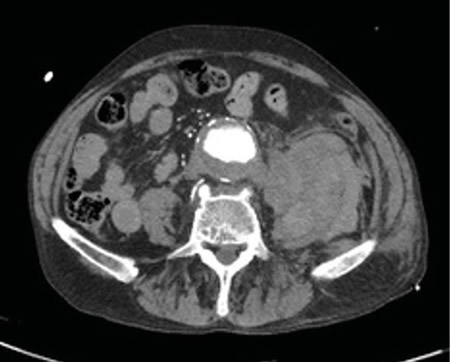

No es solo dolor lumbar: manifestación atípica del aneurisma de aorta

Not just low back pain: atypical manifestation of aortic aneurysm

La rotura de aneurisma de aorta supone el síntoma principal en hasta un 25 % de los casos de la patología de aneurisma de aorta, que constituye una entidad potencialmente mortal. También puede aparecer con menor prevalencia como lumbalgia, coxalgia e, incluso, gonalgia, no comentándolo como dolor vertebral o neuropático, sino como irritación a nivel de psoas ilíaco como primera sintomatología.

Se estima que solo en un 50 % de los casos aparece la triada clásica del aneurisma, por lo que es necesario tener un alto nivel de alerta para sospecharlo, ya que la hipovolemia puede estar contenida por un hematoma peritoneal.

Figura 1

Figura 2